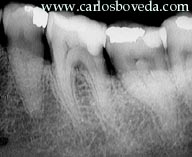

La paciente, de 58 años de edad, nos fue referida inicialmente en el año 1996 para evaluar y tratar el primer molar inferior izquierdo.

En este primer momento el molar presentó una pulpitis irreversible consecuencia de una cavidad muy profunda de caries en su aspecto distal. A nuestra consulta fue referida luego que le removieron parcialmente la caries, pero en franca comunicación con el espacio pulpar y presentando ya una molestia espontánea, aunque leve.

El tratamiento endodóntico, ejecutado en esta primera sesión, transcurrió sin contratiempos, si bien los conductos se mostraron muy pequeños y curvos, como pueden evidenciarse en las imágenes radiográficas. Al finalizarlo, se selló la cámara de abordaje con vidrio ionomérico tipo I y se refirió nuevamente para su restauración, con nuestra recomendación de incluir protección cuspídea.